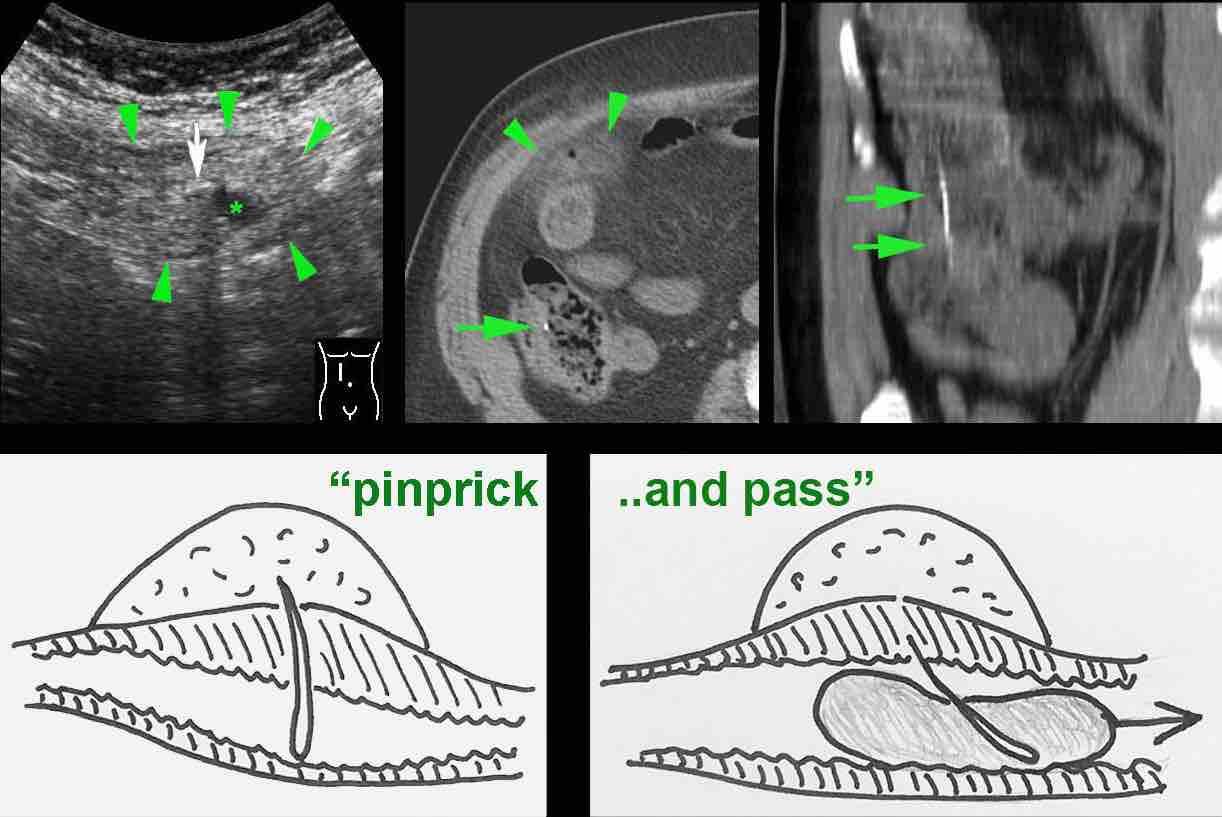

Thủng vi điểm và tự thoát (Pinprick-and-pass)

Một dị vật sắc nhọn có thể gây thủng, nhưng sau đó vẫn có thể tự thoát ra ngoài theo phân một cách bình thường (“thủng vi điểm và tự thoát”).

Bệnh nhân nam 85 tuổi này nhập viện với đau khu trú dữ dội, viêm phúc mạc khu trú và CRP 200, lâm sàng nghi ngờ viêm ruột thừa.

Siêu âm cho thấy một vùng nhỏ khu trú gồm mỡ tăng âm bị viêm (đầu mũi tên), chứa một ít dịch (*) và một phản âm khó lý giải (mũi tên trắng).

Chẩn đoán siêu âm dự kiến là viêm phần phụ mạc nối với vùng xuất huyết trung tâm nhỏ.

CT xác nhận thâm nhiễm mỡ khu trú và phát hiện thêm một bóng khí cũng như dày thành nhẹ của một quai ruột non lân cận.

Áp dụng từ gợi nhớ PSI-ABCD, tất cả các nguyên nhân đều được loại trừ, ngoại trừ dị vật sắc nhọn.

Sau khi tìm kiếm có chủ đích, một xương cá được phát hiện tại manh tràng (mũi tên xanh lá trên CT).

Rõ ràng, xương cá này đã gây ra thủng, và sau đó được đẩy đi bởi nội dung ruột non. Bệnh nhân được điều trị bằng kháng sinh đơn thuần và hồi phục hoàn toàn.